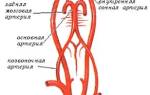

Виллизиев круг является ключевым элементом для нормального кровоснабжения всех систем нашего организма. Он образуется крупными позвоночными артериями, которые делятся на левую и правую ветви. В нормальных условиях развитие этих артерий происходит равномерно. Подключичная артерия, направляясь к черепной полости, разветвляется на входе.

Симптоматика левосторонней артериальной гипоплазии тесно связана с нарушениями кровообращения и проявляется не сразу. Гемодинамические расстройства приводят к затруднению проходимости сосудов, образованию застойных явлений и ишемии органов. Адаптационные механизмы организма могут сглаживать развитие заболевания, поэтому его серьезные последствия не проявляются мгновенно — это длительный процесс, который может растянуться на многие годы.

Первым тревожным сигналом может стать болевой синдром в области шеи позвоночника. Если при этом отсутствуют другие симптомы, то правильная диагностика может быть затруднена. Еще одним характерным признаком гипоплазии является анастомоз — соединение ответвлений крупных сосудов. Таким образом, организм пытается компенсировать недостаточное развитие позвоночных артерий. Однако этот компенсаторный механизм может утратиться при ухудшении проходимости сосудов.

Левосторонняя гипоплазия может привести к гипертензии — повышению артериального давления. Это вторичное состояние служит своеобразным сигналом о том, что организм пытается адаптироваться к возникшей ситуации.

Серьёзные изменения затрагивают область костного канала и артерии, которая в него впадает. При гипоплазии ткани головного мозга получают значительно меньше крови, что может привести к негативным последствиям.

Гипоплазия позвоночной артерии (как правосторонняя, так и левосторонняя) встречается гораздо чаще, чем многие предполагают. Около 10% населения планеты страдает от этой патологии. У большинства людей компенсаторные механизмы организма достаточно развиты, что позволяет им долгое время справляться с этим заболеванием.